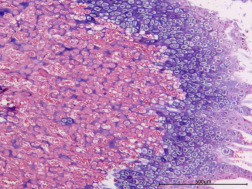

正常組、骨折組

圖1 HE染色圖 40X

樣本中細(xì)胞核被蘇木精染成藍(lán)色;細(xì)胞質(zhì)被伊紅染成深淺不同的粉紅色至深紅色。